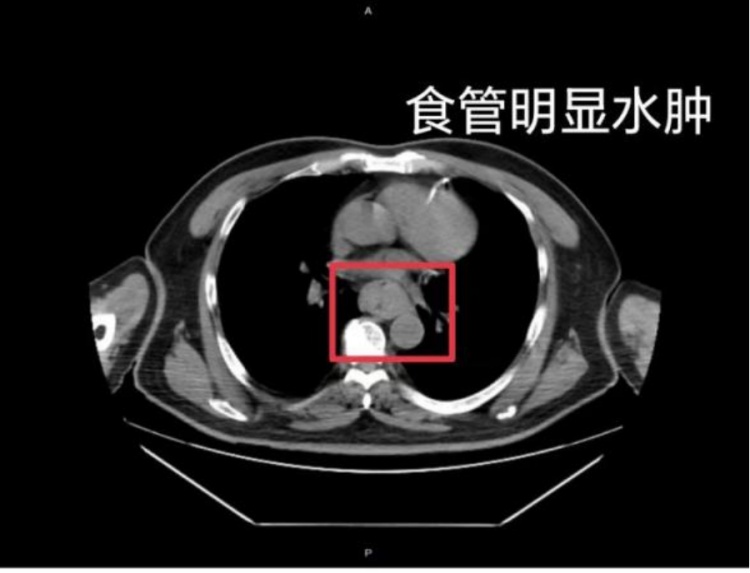

这样的情况并非个例,同样在近日,福州一位网友分享了自己因吃了一碗很烫的福鼎肉片导致呕血,并查出食管水肿的经历。

据网友回忆,“自己去厕所尝试呕吐时,直接呕出了血,一大口鲜血从嘴里喷出,总共吐了两次。”CT结果显示,他的食管全部水肿损伤。